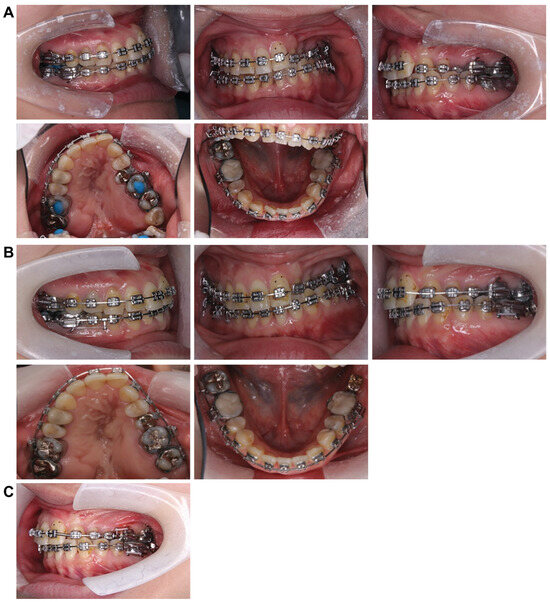

5.1. Facial Appearance Findings (Figure 9A)

The frontal view showed facial symmetry, with the previously elevated left corner of the mouth at rest and a pronounced left cant while smiling, which was resolved and improved. In the lateral view, a noticeable improvement in the protrusion of the lower lip was observed. Furthermore, the E-line measurements indicated that the upper lip was at 0 mm and the lower lip was at +5.0 mm, reflecting a reduction in lower lip protrusion compared with the initial evaluation. The vertical balance approached an approximately 1:1 ratio, with no significant changes observed in the nasolabial angles.

Figure 9.

Post-treatment record. (A) Facial photographs. (B) Intraoral photographs. (C) a: at the time of initial examination: anterior width 25.1 mm, posterior width 38.0 mm; b: at the end of preoperative correction: anterior width 29.1 mm, posterior width 38.7 mm; c: immediately before retention: anterior width 34.2 mm, posterior width 43.8 mm. (D) Panoramic radiograph. (E) Lateral and front cephalogram.

5.2. Intraoral Findings (Figure 9B,C)

Constriction of the left maxillary dental arch improved, resulting in the maxillary and mandibular arches forming an ovoid shape. The left crossbite was corrected, achieving a normal relationship. The overbite measured +2.2 mm, and the overjet was +2.0 mm, with the molar relationship on the right and left sides classified as Angle Class II and I, respectively. The anterior width of the maxillary dental arch increased from 29.1 mm at the end of preoperative orthodontics to 34.2 mm. Similarly, the posterior width expanded from 38.7 mm to 43.8 mm, yielding an overall improvement of approximately 5.0 mm in width compared with the end of preoperative orthodontics. However, the arch width before retention remained unchanged. A space remained between the maxillary left central incisor and canine following segmentation, and the mandibular left molar had not yet received its final prosthetic restoration. Owing to the patient’s scheduling convenience, the brackets were removed before the final prosthetic restoration could be completed.

5.3. Panoramic Cephalometric Radiograph (Figure 9D)

The roots of the teeth appeared parallel, indicating good overall parallelism. Furthermore, a carious-like radiolucency was observed distal to the left mandibular second premolar. At the patient’s request, retention was performed before the placement of a prosthetic restoration for the left mandibular second molar. Therefore, there are plans to proceed promptly with prosthetic restoration soon.

5.4. Lateral and Frontal Cephalometric Radiographs (Figure 9E)

The SNA increased slightly from 73.0° to 75.0°, indicating a slight forward positioning. However, the SNB decreased from 72.0° to 70.0°, suggesting a posterior positioning of the Mand.P with a clockwise rotation, leading to an increase in the mandibular plane angle from 35.0° to 37.0°. Frontal cephalometric radiography showed that the cant had resolved, with the Menton and facial midline nearly aligned. In addition, the deviations of the maxilla and mandible improved, resulting in a symmetrical facial appearance.